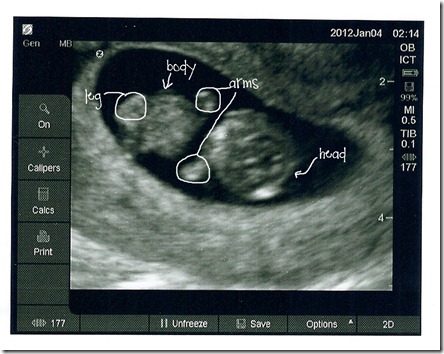

And . . .  Introducing our little peanut:

They did change my due date a  couple of days, which is fine. But I got to see my little baby moving its hands around, and the little heart fluttering, and I’m already in love!

For those not fluent on your fuzzy dots, I edited the picture for you (it’s SO much easier to see in person than in a picture! and the other leg is hiding behind the cord right now, but it’s there!)

baby explain